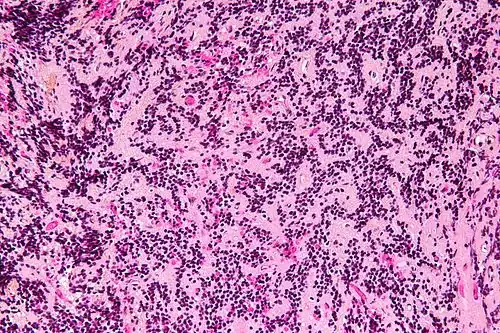

Пинеобластомы при макроскопическом исследовании не имеют четких границ, характеризуются инвазивным, инфильтрирующим ростом. Консистенция мягкая, хрупкая, цвет розово-серый, часто с некрозами. Микроскопически опухоль обладает высокой клеточностью, представлена листами плотно расположенных небольших клеток. Ядра неправильной формы, гиперхроматичные, ядерно-цитоплазматическое отношение высокое. Розетки редки, но могут наблюдаться розетки Гомера Райта и розетки Флекснера-Винтерштайнера. Появление розеток Флекснера-Винтерштайнера говорит о ретинобластной дифференцировке опухоли. Митотическая активность высокая.